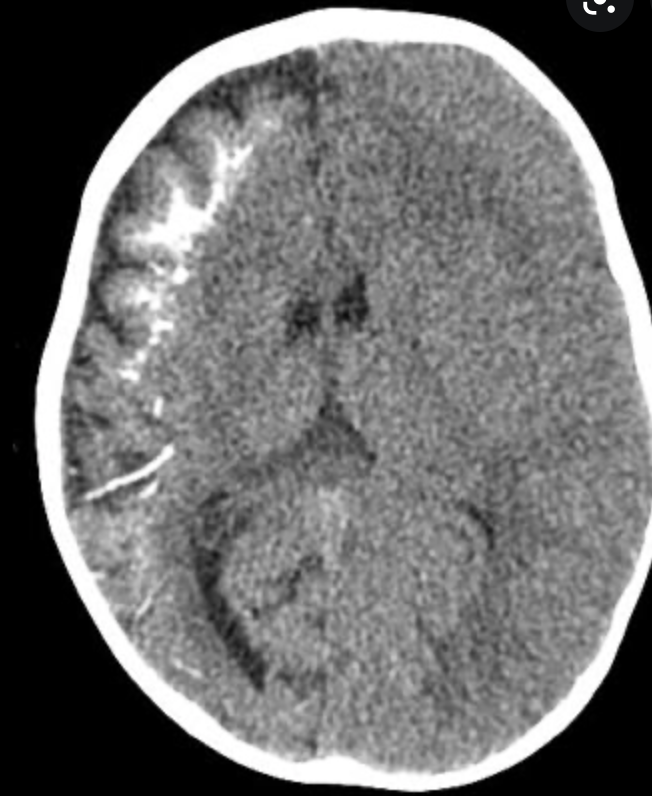

Sturge-Weber syndrome, or encephalotrigeminal angiomatosis, is a phakomatosis characterised by facial port wine stains and pial angiomas.

Approximately a third of patients have choroidal or scleral angiomatous involvement, which may be complicated with retinal detachment, buphthalmos or glaucoma 1.

Dyke-Davidoff-Masson syndrome is a condition characterised by hemicerebral atrophy/hypoplasia secondary to brain insult usually in fetal or early childhood period and is accompanied by ipsilateral compensatory osseous hypertrophy and contralateral hemiparesis.

It is characterised by:

thickening of the skull vault (compensatory)

enlargement of the frontal sinus (also ethmoidal and mastoid air-cells)

elevation of the petrous ridge

ipsilateral falcine displacement

capillary malformations (are a novel finding for children with Dyke-Davidoff-Masson syndrome) 6

In some sources, it is equated to hemispheric infarction, whereas in other sources any cause of cerebral hemiatrophy is included.